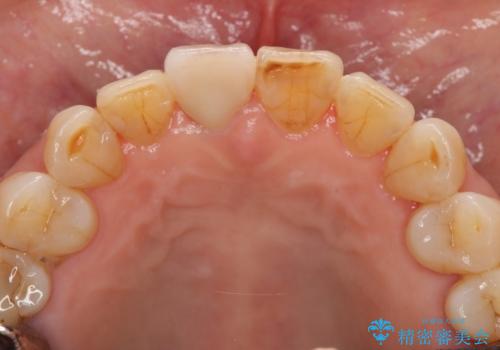

天然歯を模した ハイグレードオールセラミッククラウン

ジルコニアクラウンエクセレントについて

当法人でご提案できる最上位クラスのジルコニアクラウンです。

透明感や周囲の歯との色の調和に大変ご満足いただけました。